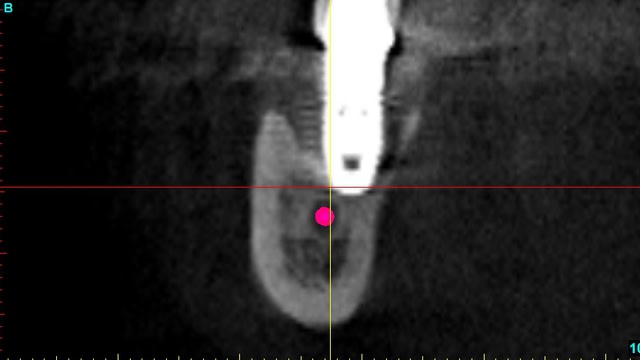

quelques images en 3 D...

Bernard cross section apfhj5 - Eugenol

Bernard cross section  2  ctt7jw - Eugenol